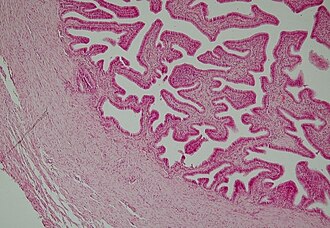

Histologija

Jajovod se sastoji od četiri sloj, neki od kojih su nejednake debljine u pojedinim segmentima:

- Serozna ovojnica - oblaže jajovod izvana

- Supserozni sloj - nalazi se ispod seroze

- Mišićni sloj - sastoji se od glatkih mišića, i postaje sve tanji kako se udaljava od maternice

- Sluznica - epitel koji iznutra oblaže jajovod, podložan je promjenama povezanim sa menstruacijskim ciklusom i sastoji se od tri vrste stanica (sekrecijske cilindrične, stanice sa trepetljikama i štapićaste). Ispod epitel nalazi se rahlo vezivo, lamina proprija.